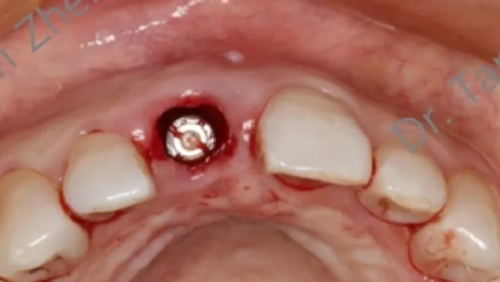

术中技巧:

-

在即刻种植完成后,我们从腭侧相邻位置采取软组织,制作一个旋转瓣。

这个旋转瓣带有一个蒂部,保留了一部分血液循环,以减少组织坏死的风险。

旋转瓣通过转换位置,覆盖填补即刻种植后留下的牙槽窝。

这一过程有助于局部骨增量的完成,即在种植区域增加骨组织,以支持种植体的稳定性。

术后愈合:

旋转瓣的使用可以保护种植区域,使其在术后正常愈合,减少外界干扰。

这种保护作用对于避免骨移植材料暴露和种植体周围感染至关重要。